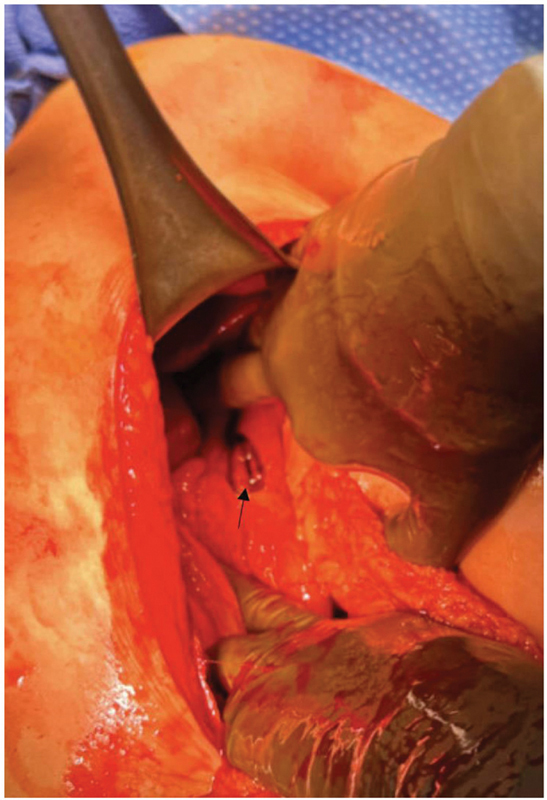

Peptic ulcers and complications, such as perforation, are rare during pregnancy and the puerperium. Accordingly, many clinicians may place these diagnoses low on their differential diagnosis. We present two case reports of primigravida, advanced maternal-age females with a history of irritable bowel syndrome and nonsteroidal anti-inflammatory drug use found to have perforated duodenal ulcers after cesarean section. Postpartum surgical abdomens may not present with classic guarding and rigidity. A low threshold for imaging and identification of risk factors is critical to timely diagnosis and management.

Abstract Image